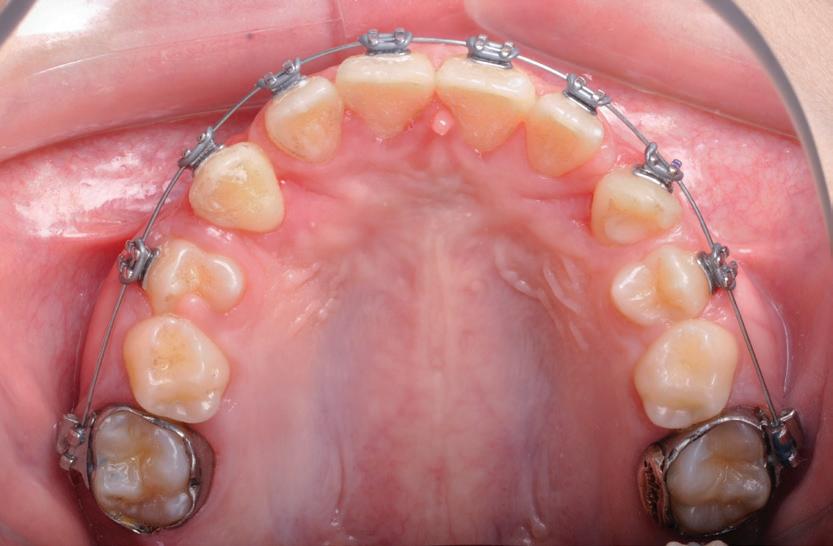

Pentru tracționarea dinților impactați, este importantă utilizarea fie a unui arc de sârmă cu bază dreptunghiulară din oțel inoxidabil, fie o bară transpalatinală groasă, cu rigiditate adecvată. Acest lucru este esențial în special la caninii incluși palatinal. Evitarea utilizării arcurilor flexibile poate permite un control mai bun al efectelor adverse asupra dinților adiacenți în timpul tracțiunii. Se poate obține o ancorare suficientă în interiorul arcadei, prelucrând secvența până la arcurile 0,019 x 0,025 într-un slot de 0,022. Acest lucru previne deformarea arcurilor, deschiderea ocluziei din cauza tracțiunii, intruziunea dinților adiacenți și alte efecte adverse conexe. S-au utilizat diferite elemente externe, cum ar fi porțile batante, arcurile transpalatinale, extensoarele Hass, arcurile guad helix, expansoarele Hyrax și dispozitivele de ancorare temporară (temporary anchorage devices, TAD), ca aparate de ancorare alternative. În cazul unei bare transpalatinale, obiectivul este de a utiliza brațele de extensie în consolă pentru a tracționa caninul impactat în palat. Aceasta este urmată de tracțiunea caninului în poziția sa finală, utilizând arcuri de poziționare sau alte metode pentru a aduce dintele inclus pe arcada dentară (fig. 4, 5).

Figurile: 4. Accesoriu de tipul porții batante utilizat pentru tracționarea directă a unui canin palatinal gestionat cu expunere deschisă.

5. Expunerea deschisă a unui canin cu impactare palatinală; s-a utilizat o bară transpalatinală ca sursă de ancorare cu un braț extensibil conceput pentru tracțiune directă.

6, 7. Utilizarea lamboului repoziționat apical pentru a gestiona caninii bilaterali cu impactare facială. După expunere, s-a practicat și frenectomia și au fost plasate bracketuri bilaterale (fig. 6). S-a realizat tracțiunea ortodontică, ce a permis poziționarea corespunzătoare a ambilor canini pe arcada superioară (fig. 7)

apoi direcționarea vestibulară a caninului (fig. 8, 9).